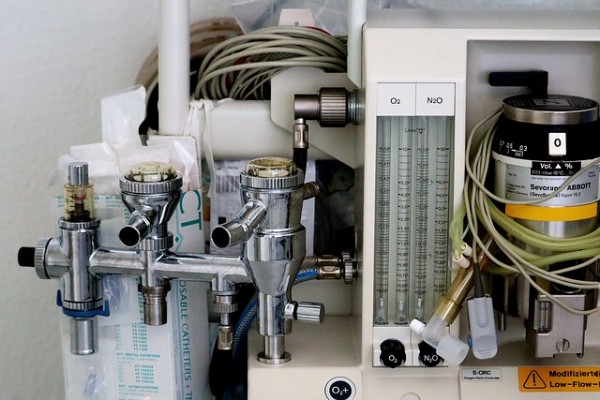

Anaesthesia